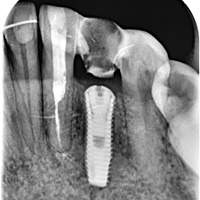

Po zabiegu transplantacji zęba rozwinęła się resorbcja i trzeba było usunąć ząb. Zdjęcia po dobudowie kosci, implantacji i leczeniu protetycznym.